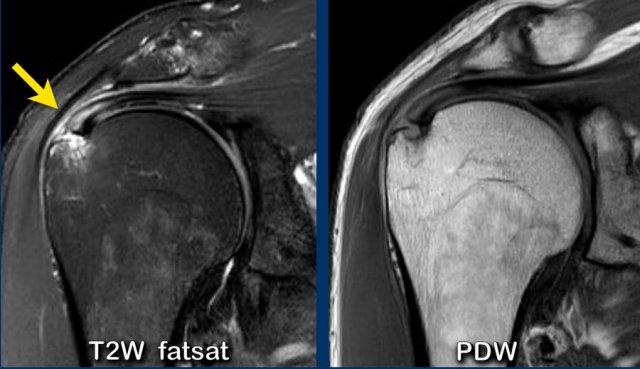

Hình ảnh

Trên chuỗi xung T2W có một tổn thương rách mặt túi hoạt dịch kích thước lớn.

Lưu ý rằng trên MRI khớp có thuốc tương phản từ, tổn thương rách không quan sát thấy do thuốc tương phản từ nội khớp không thể tiếp cận vị trí khuyết trong gân.